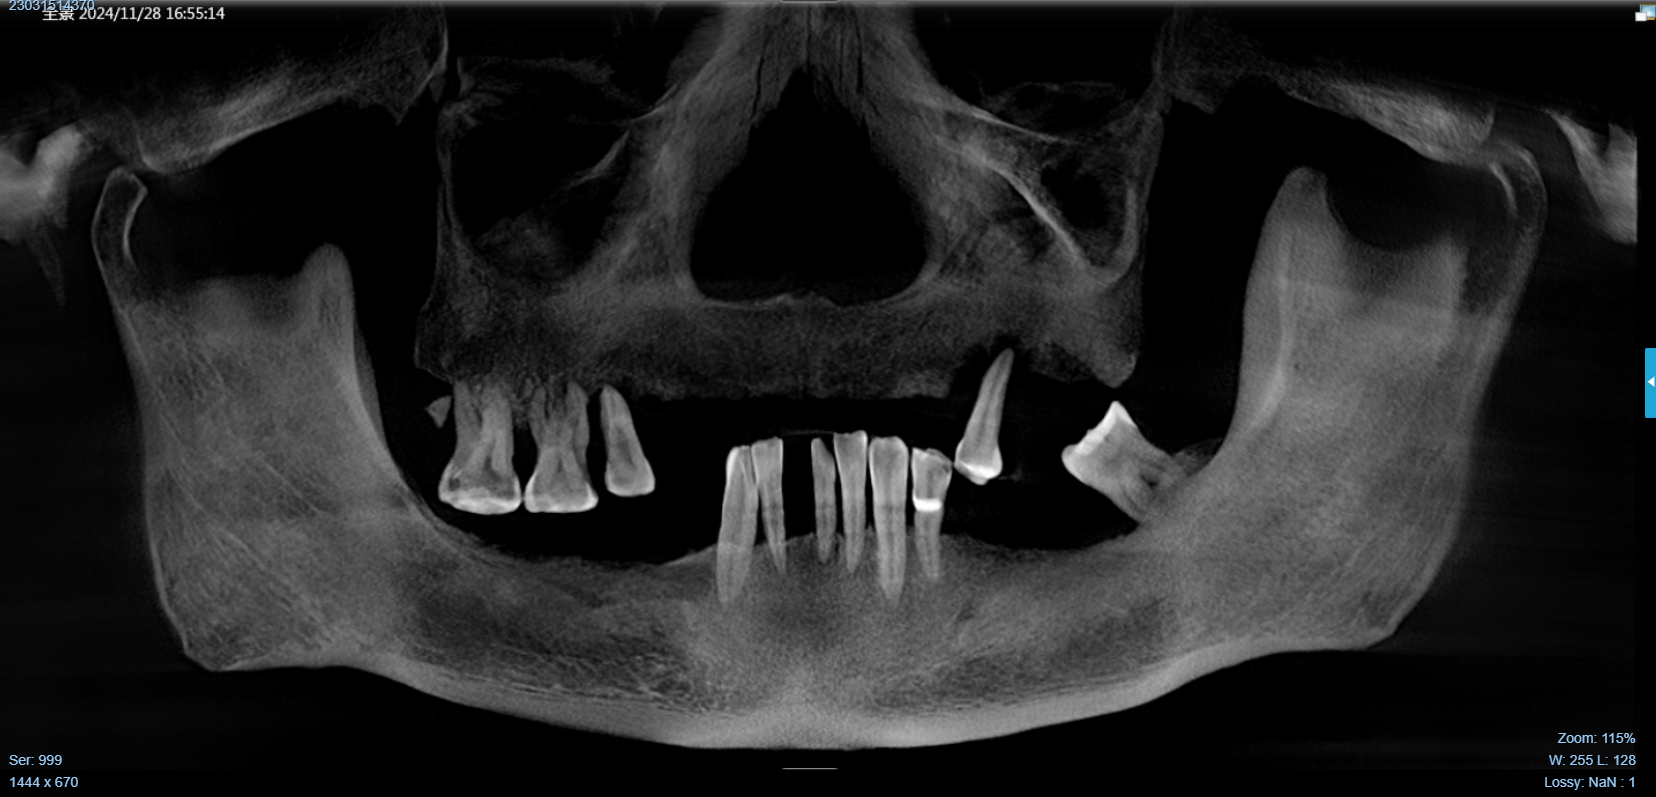

该患者就是因牙周病导致牙齿松动脱落,我们通过在半口牙槽骨上植入8颗种植体,然后在种植体上安装连桥牙冠,从而恢复半口牙齿的咀嚼功能和美观。相对于传统的种植修复方式缺一颗种一颗。4-8颗种植体的种植手术创伤相对较小,大大的减少了患者的疼痛感。